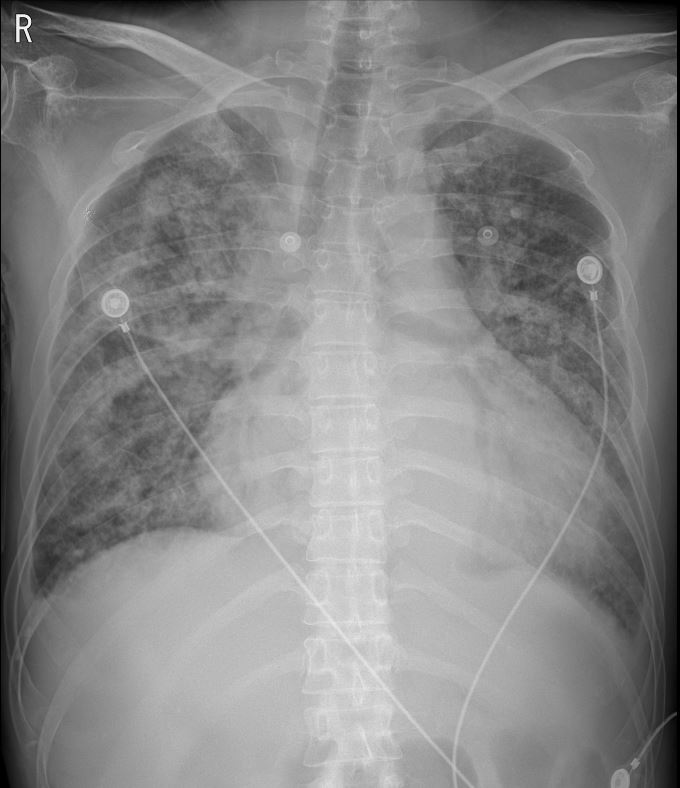

우리병원 응급실에 도착한 상태에서 환자의 의식은 회복된 상태였고, 혈압이나 심박수는 안정되어 있었다. 하지만 산소요구량이 높은 상황에서 양측 폐의 호흡음이 좋지 않았다. 발열 또한 동반되어 있는 상태였기에 호흡기감염병을 의심하여 격리실에 격리된 상태에서 코로나 검사 결과를 기다리며 흉부 CT를 촬영하게 되었고, 환자의 양측 폐는 심각한 정도의 폐렴이 있음이 확인되었다.